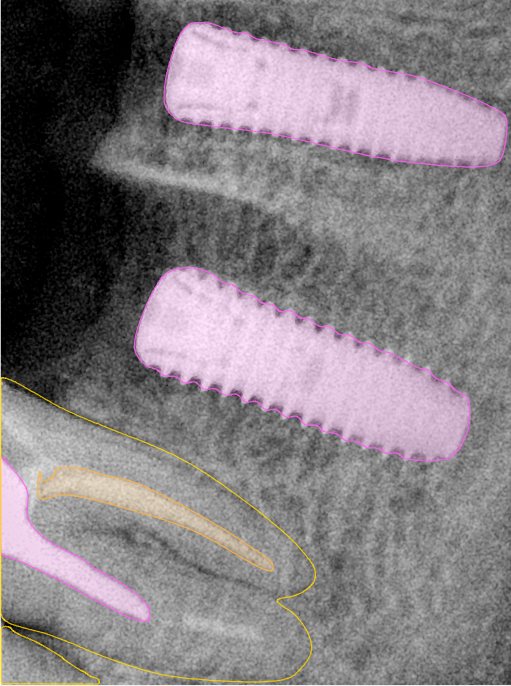

CR/DR 牙齿分割阶段记录

当前进展

- 完成了 CR/DR 牙齿相关分割训练

- 当前结果已经达到阶段预期,但仍有细节问题需要继续处理

相关测试

遇到的问题

- 训练过程中出现过 mask 下移问题

- 部分结果会出现 box 填充异常

- mask 边缘仍然有比较明显的锯齿感